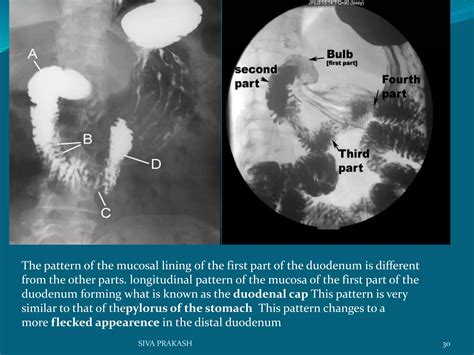

The Small Bowel Follow Through (SBFT) is a radiological examination that uses X-rays to visualize the small intestine. This procedure is particularly useful for detecting abnormalities such as strictures, obstructions, tumors, and inflammatory conditions like Crohn’s disease. The SBFT involves ingesting a barium solution, which coats the lining of the small intestine, making it visible on X-ray images.

• X-ray Imaging: As the barium solution moves through the small intestine, a series of X-ray images are taken at regular intervals. This allows the radiologist to observe the movement of the barium and identify any abnormalities.

Interpreting the results of an SBFT requires expertise in radiology. The radiologist will examine the X-ray images for any signs of abnormalities. Common findings include: